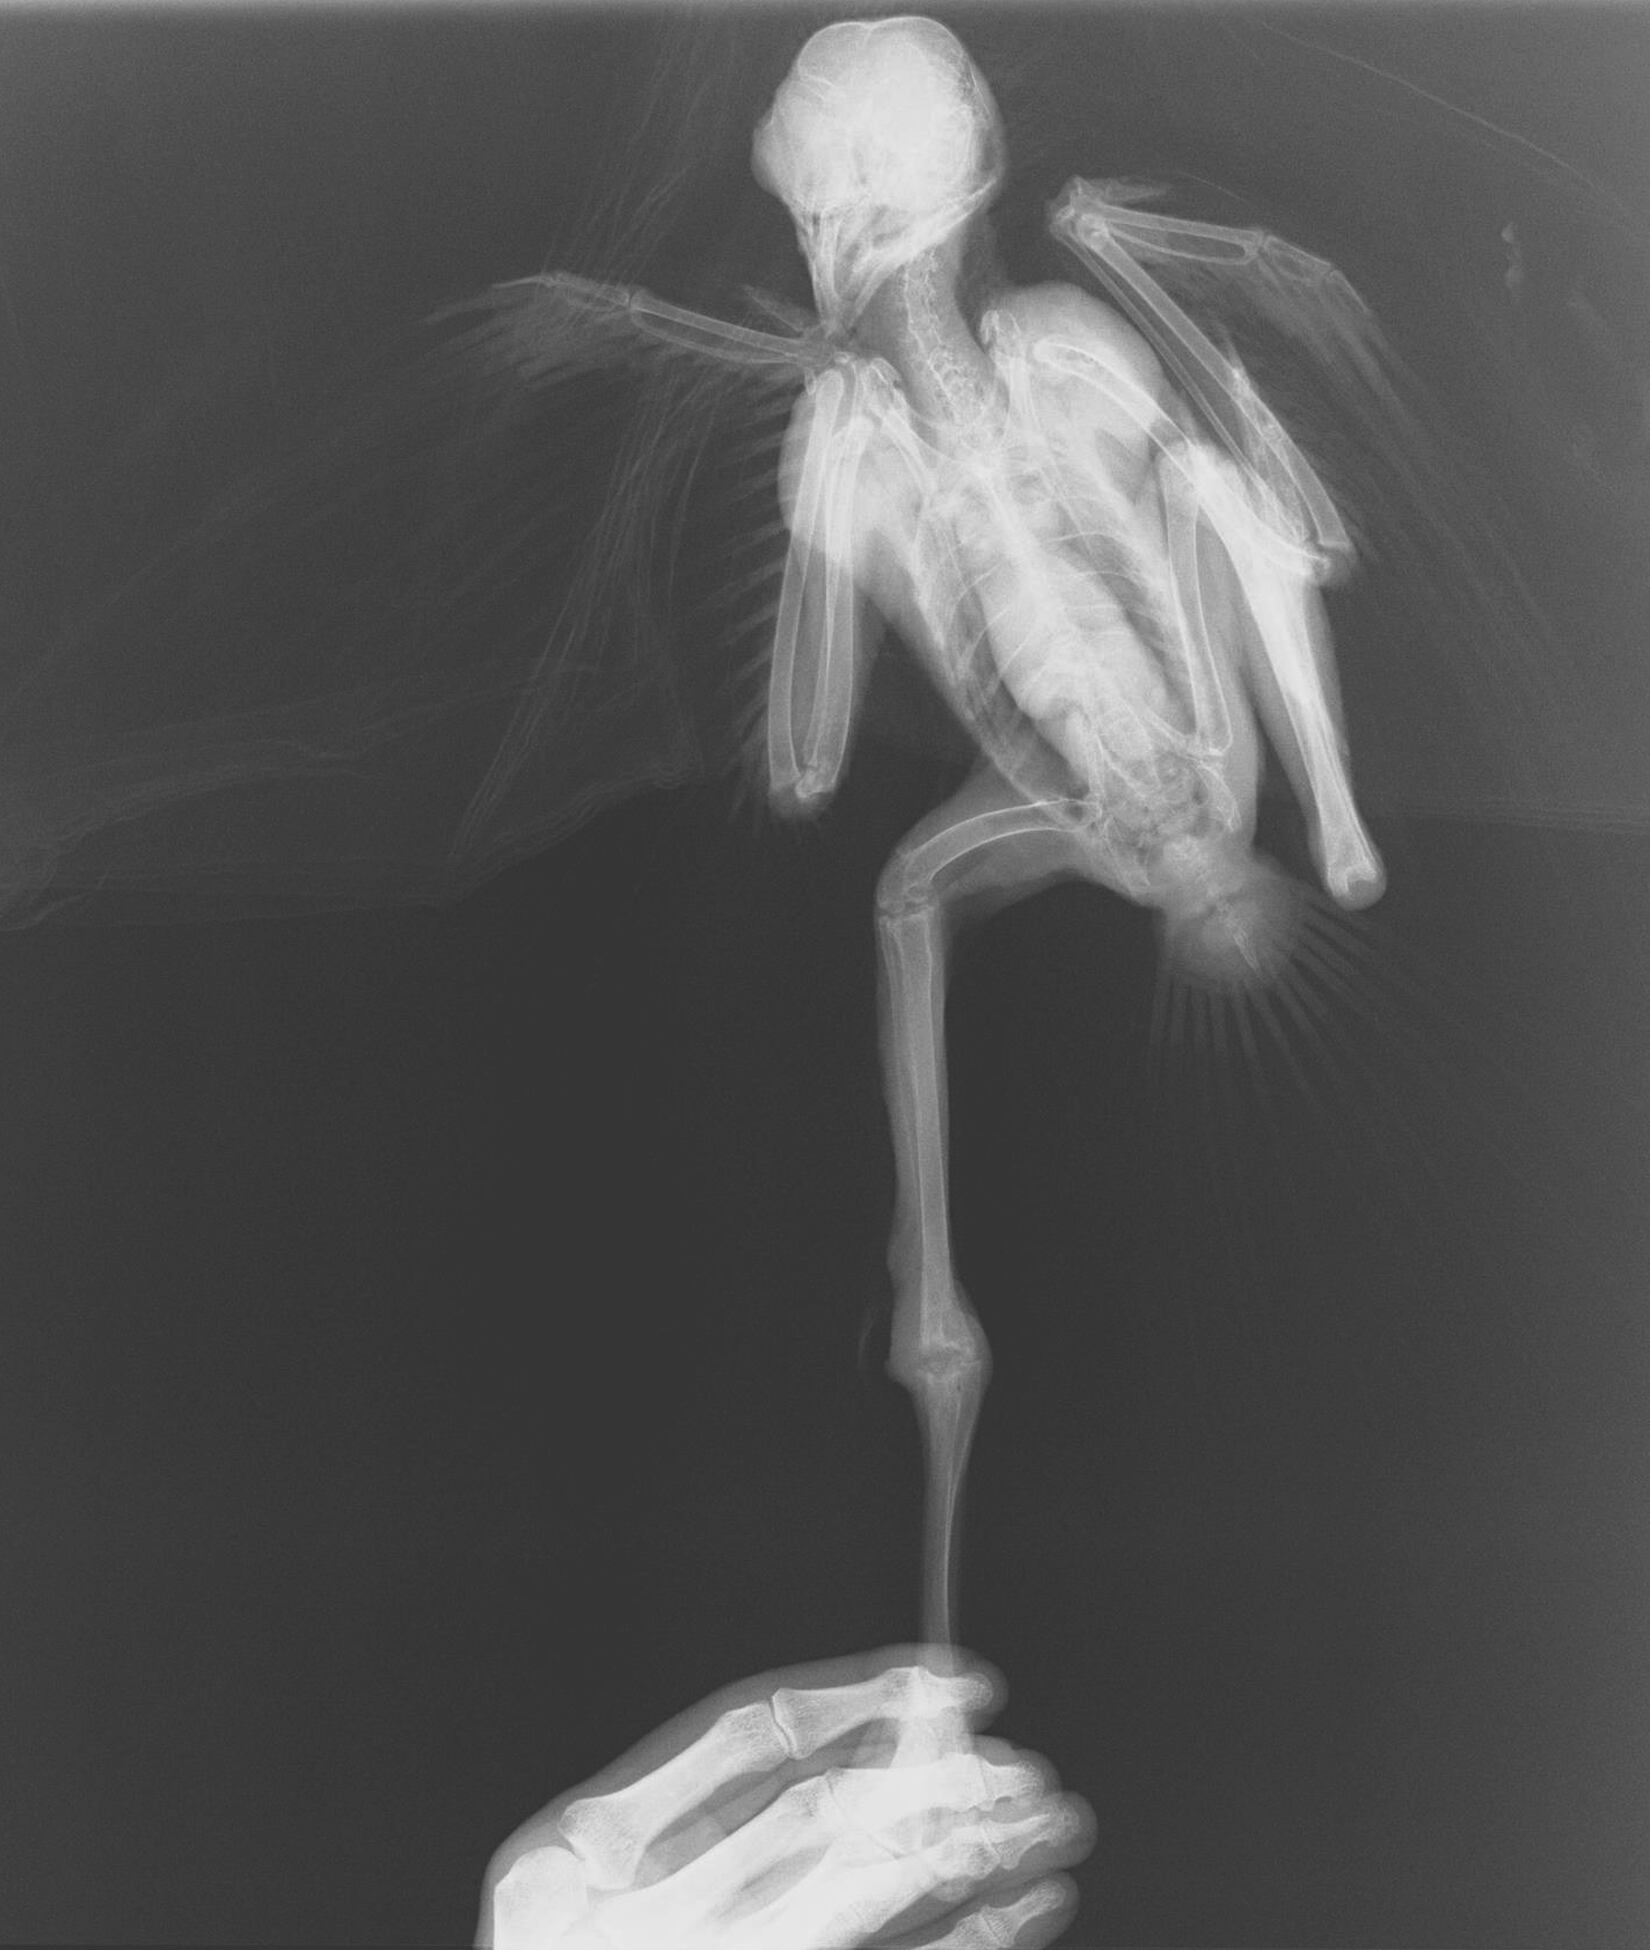

El enfoque de las postales, coloradas en blanco y negro, evitan la crudeza visual, pero no omiten el dolor: evocan el malestar de un pelícano con un anzuelo incrustado en una de sus patas, o uno de los tantos monos fracturados tras caer al asfalto electrocutados.